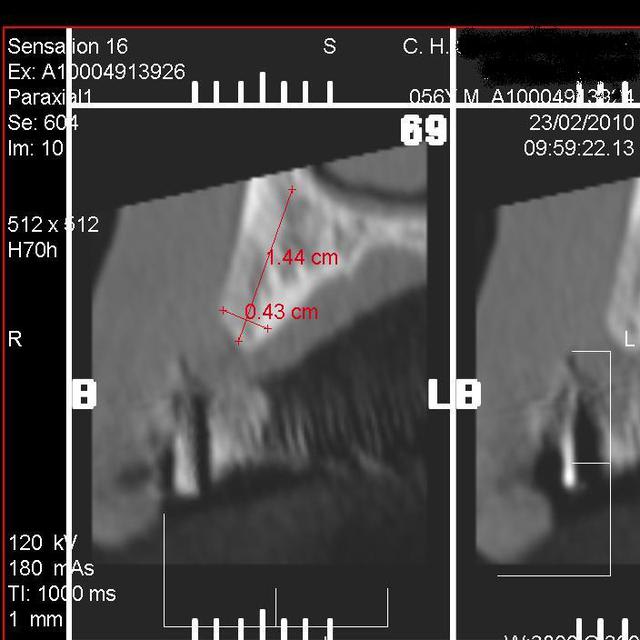

Je vais bientôt poser un implant pour remplacer une canine maxillaire perdu par fracture radiculaire ( richmond).

Mon hésitation concerne la taille de l'implant car manifestement je ne peux mettre plus gros qu'un 4.1 X 13mm. La longueur me parait suffisante mais le diamètre me parait léger pour une canine....

Je serais trés certainement obligé d'utiliser un pilier angulé à 20°